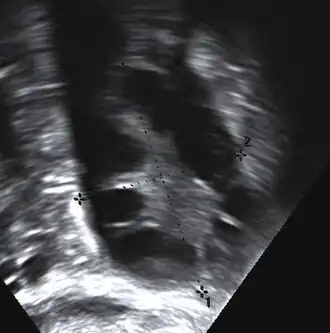

Gynecologic ultrasonography first looks for small ovarian follicles.[75] To count as polycystic ovaries, at least 20 follicles need to be present, smaller than 9 mm. This used to be 12 in older diagnostic criteria.[16] A less clear marker of PCOS is enlarged ovaries.[75] Ovary need to be at least 10 cm3 to count.[16] For sexually active individuals or those that agree, a transvaginal ultrasound approach is preferred. Alternatively, AMH levels can be tested in the blood.[75] Laparoscopic examination may reveal a thickened, smooth, pearl-white outer surface of the ovary. This would usually be an incidental finding if laparoscopy were performed for some other reason, as it would not be routine to examine the ovaries in this way to confirm a diagnosis of PCOS.[78]

In case medication and lifestyle interventions are ineffective, infertility can be treated with a laparoscopic procedure called "ovarian drilling", which involves puncture of 4–10 small follicles with electrocautery, laser, or biopsy needles.[98] This procedure can induce ovulation, typically leads to a single pregnancy, but other risks may be higher compared to medication.[10][99] Ovarian wedge resection is no longer used as much due to complications such as adhesions and the presence of frequently effective medications.[100]